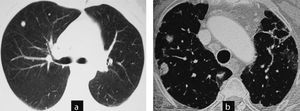

This patient was a 56-year-old woman, diagnosed with RA 5 years prior, smoker, and positive RF. A chest X-ray taken due to chest pain detected lung nodules. Computed tomography of the thorax found rounded nodules of 1–2cm cavitated, progressing in size and complicated by a pneumothorax. She underwent node resection surgery and an open pleural biopsy with a diagnosis of rheumatoid nodules. In subsequent tests all nodules disappeared.

Cases 2 and 3. Evolution of cavitated nodules. (a) and (b) Case 2: cavitated rheumatoid nodules that increase in size. The case was complicated and open pneumothorax produced a cavitated nodule on the pleura (pneumothorax image not shown). (c) and (d) Case 3: rounded subpleural nodules, in a patient with signs of interstitial lung disease. Control computed tomography of nodules show a slight decrease in size and cavitation (arrow).

This was a 53-year-old patient, diagnosed with palindromic rheumatism 6 years prior, and a smoker. RF has slowly turned positive. Interstitial lung disease associated with no respiratory symptoms. In a control CT, we detected, rounded subpleural lung nodules. Monitoring was proposed and computed tomography at 6 months shows that the nodules decreased in size and one of them had cavitated.